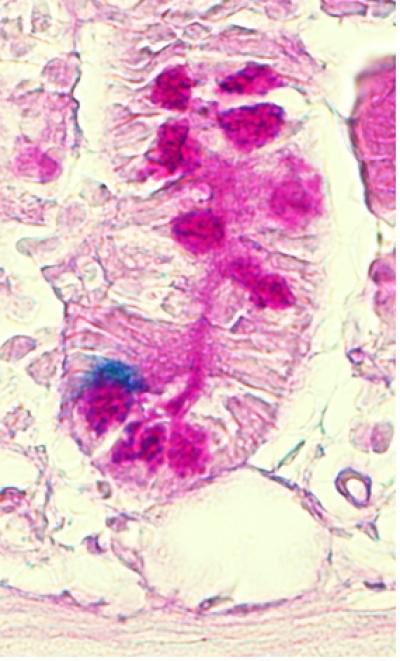

This is a stem cell (blue) from the intestinal crypt.

Norifumi Takeda, Raj Jain and Jon Epstein, Perelman School of Medicine, University of Pennsylvania